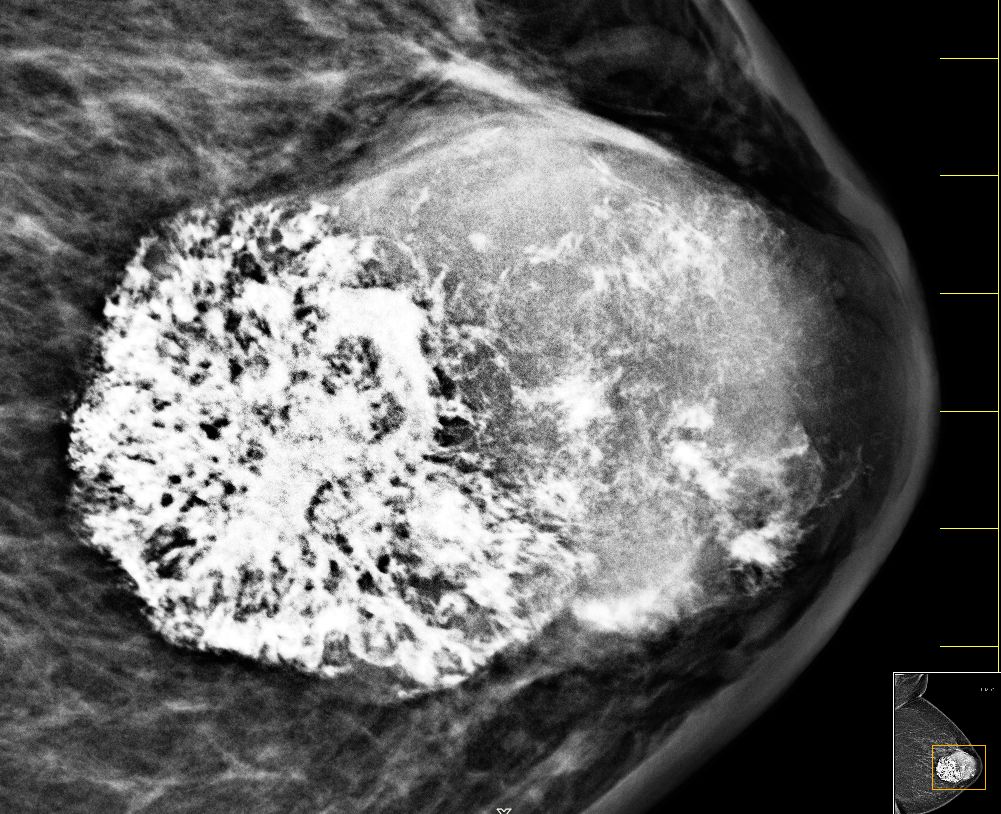

| Fall | 72-jährige Frau, bei der vor 5 Jahren ein gutartiger Tumor diagnostiziert wurde. Vor 8 Monaten war der Tumor auf 4cm angewachsen. Die Exzision wurde empfohlen. Jetzt war der Tumor 66 mm groß, sehr hart und teilweise verkalkt. | |||

| vor OP | Mammographie links MLO.![]() |

Vergrößerung.![]() | ||